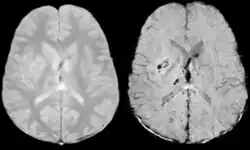

Stroke and hemorrhage

Diffusion weighted imaging offers a powerful means to detect acute stroke. Although it is well known that gradient echo imaging can detect hemorrhage, it is best detected with SWI. In the example shown here, the gradient echo image shows the region of likely cytotoxic edema whereas the SW image shows the likely localization of the stroke and the vascular territory affected (data acquired at 1.5 T).

The bright region in the gradient echo weighted image shows the area affected in this acute stroke example. The arrows in the SWI image may show the tissue at risk that has been affected by the stroke (A, B, C) and the location of the stroke itself (D). The reason that we are able to see the affected vascular territory could be because there is a reduced level of oxygen saturation in this tissue, suggesting that the flow to this region of the brain could be reduced post stroke. Another possible explanation is that there is an increase in local venous blood volume. In either case, this image suggests that the tissue associated with this vascular territory could be tissue at risk. Future stroke research will involve comparisons of perfusion weighted imaging and SWI to learn more about local flow and oxygen saturation.